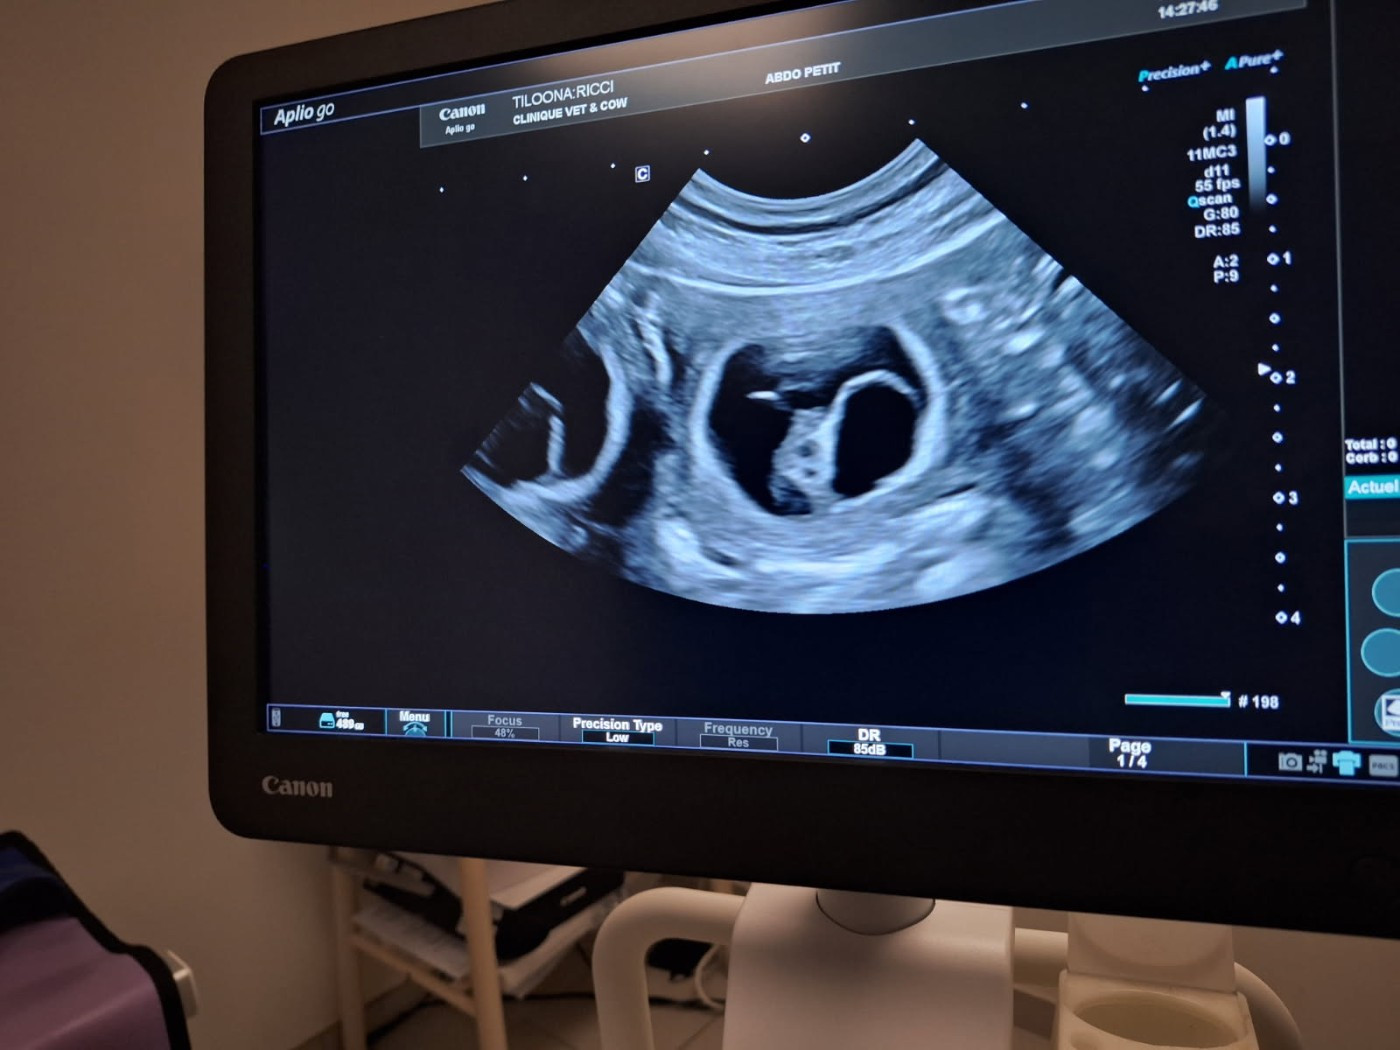

Bébés Tiloona 2025